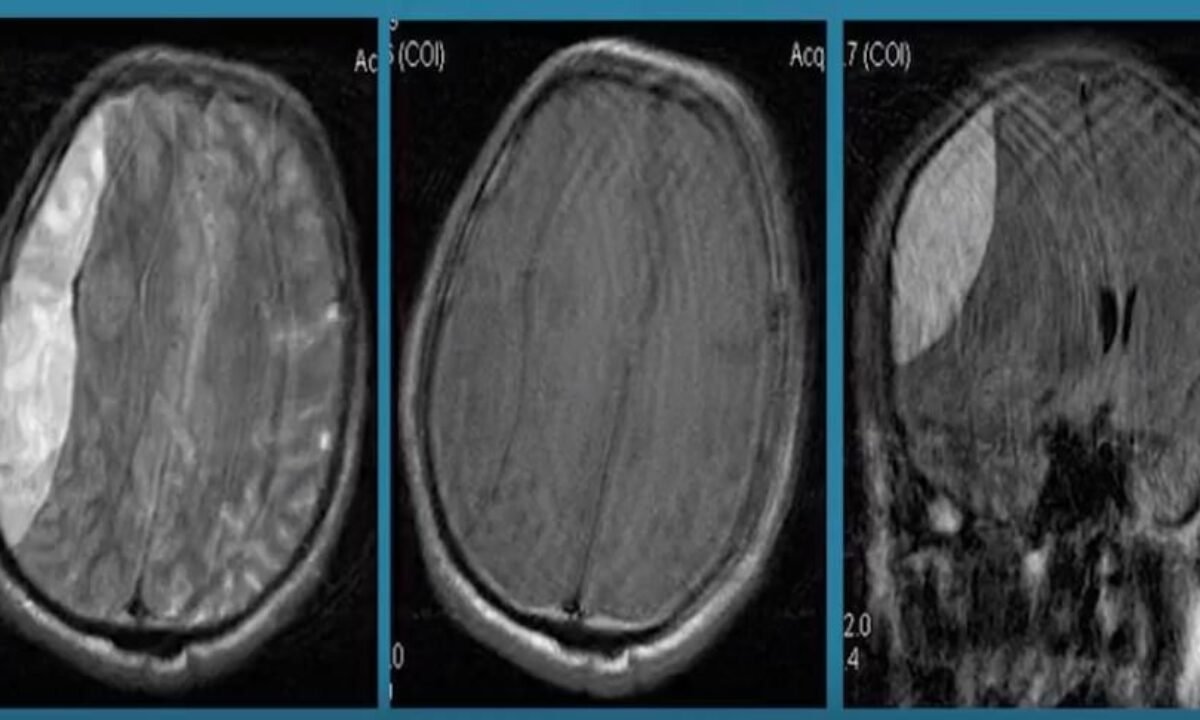

Субдуральна гематома – це скупчення крові між твердою мозковою оболонкою та мозком. Це може статися, коли судини головного мозку розриваються внаслідок травми, і кров заповнює місце, де її бути не повинно. Ось і все, що треба знати в контексті визначень. Але…